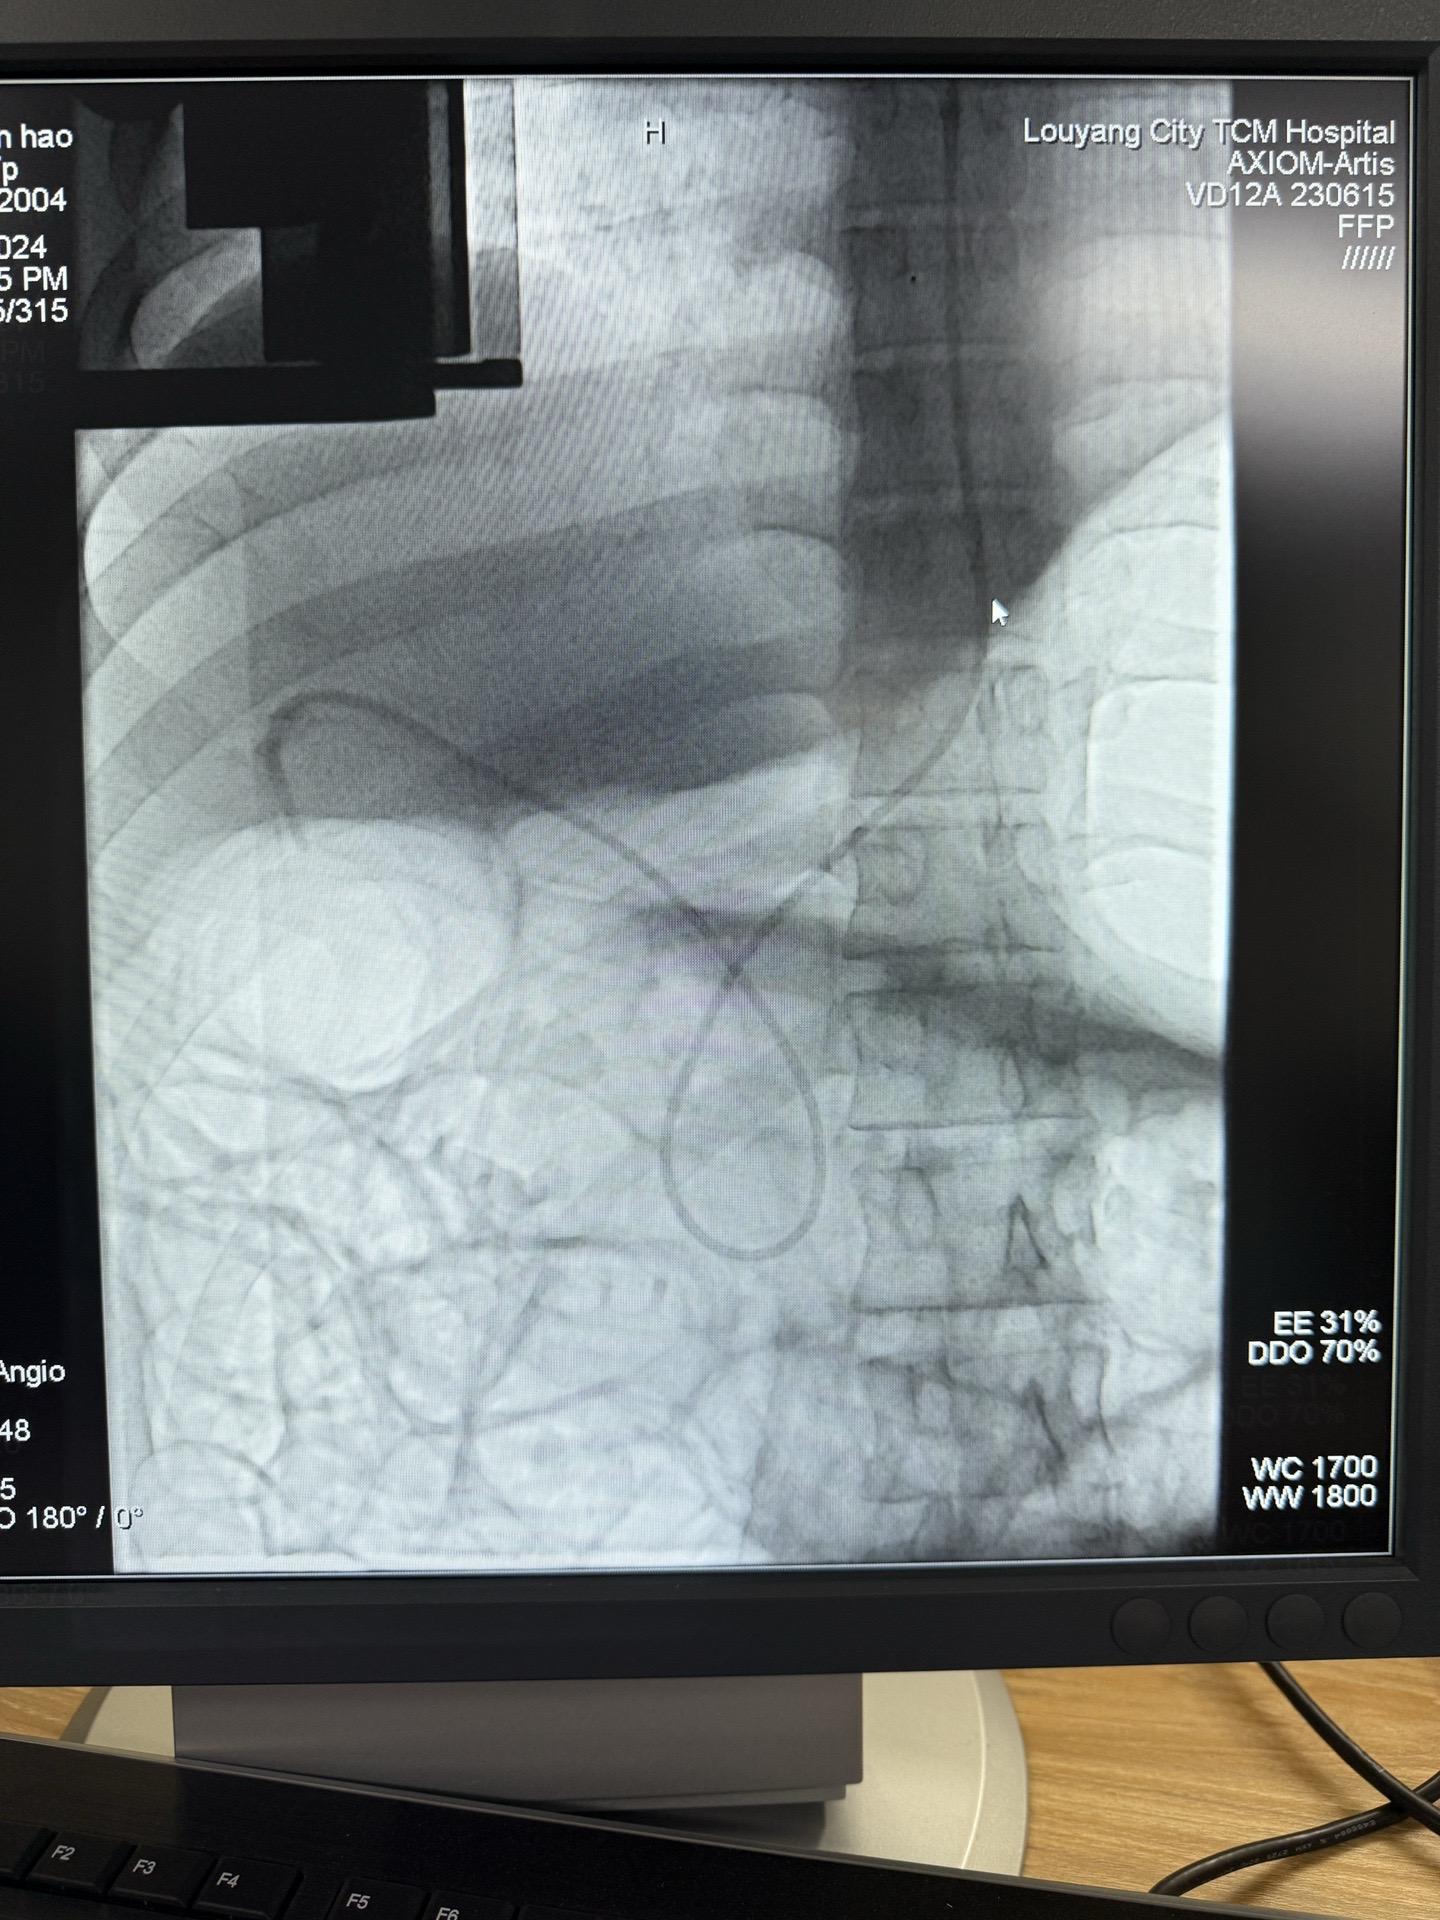

十二指肠镜能解决部分胆囊结石是不是很神奇。各大医院都在尝试通过ERCP的解决胆囊结石胆囊息肉的问题,我们也在努力,这条路不好走,但我们相信,随着技术的进步,最终胆囊结石可能不需要外科开刀!